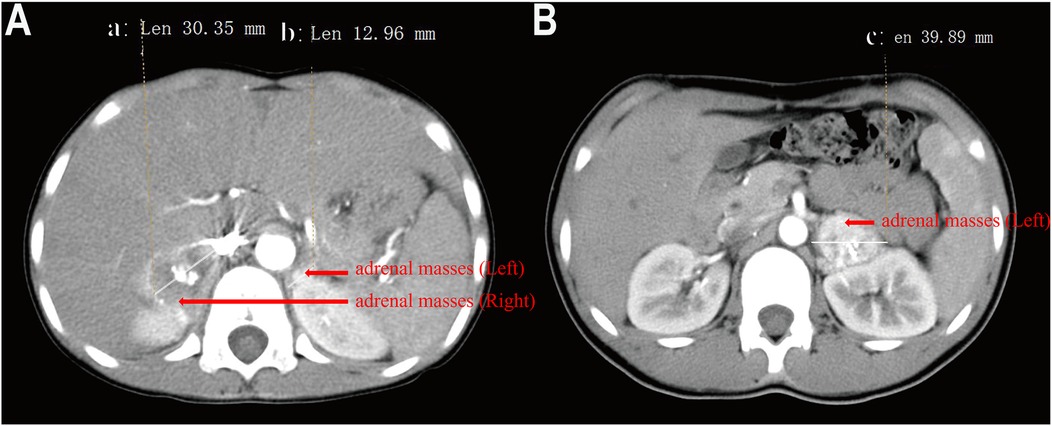

Case 1: A pediatric patient was diagnosed with multiple PGL, located on the bladder roof and left iliac vessel wall, in conjunction with an abdominal aortic malformation (Figure 1). The patient was treated with oral phenoxybenzamine to control blood pressure, reaching the maximum dose of 60 mg/day, and propranolol was added to manage heart rate. Blood pressure, heart rate, and hematocrit were optimized to within surgical thresholds before proceeding with surgery. During the operation, the bladder tumor was successfully resected, and intraoperative exploration revealed that the tumor on the left iliac vessel wall did not affect the circulation, so a biopsy was performed instead of resection. Postoperative pathology confirmed that the bladder tumor was a secretory paraganglioma, while the tumor on the iliac vessel wall was non-secretory. The patient has been followed up regularly for 7 years, with no evidence of recurrence or metastasis.

Figure 1. Enhanced pelvic CT of a child with pheochromocytoma. (A) Mass at the top of the bladder, (B) Mass on the wall of the left iliac vessels.).